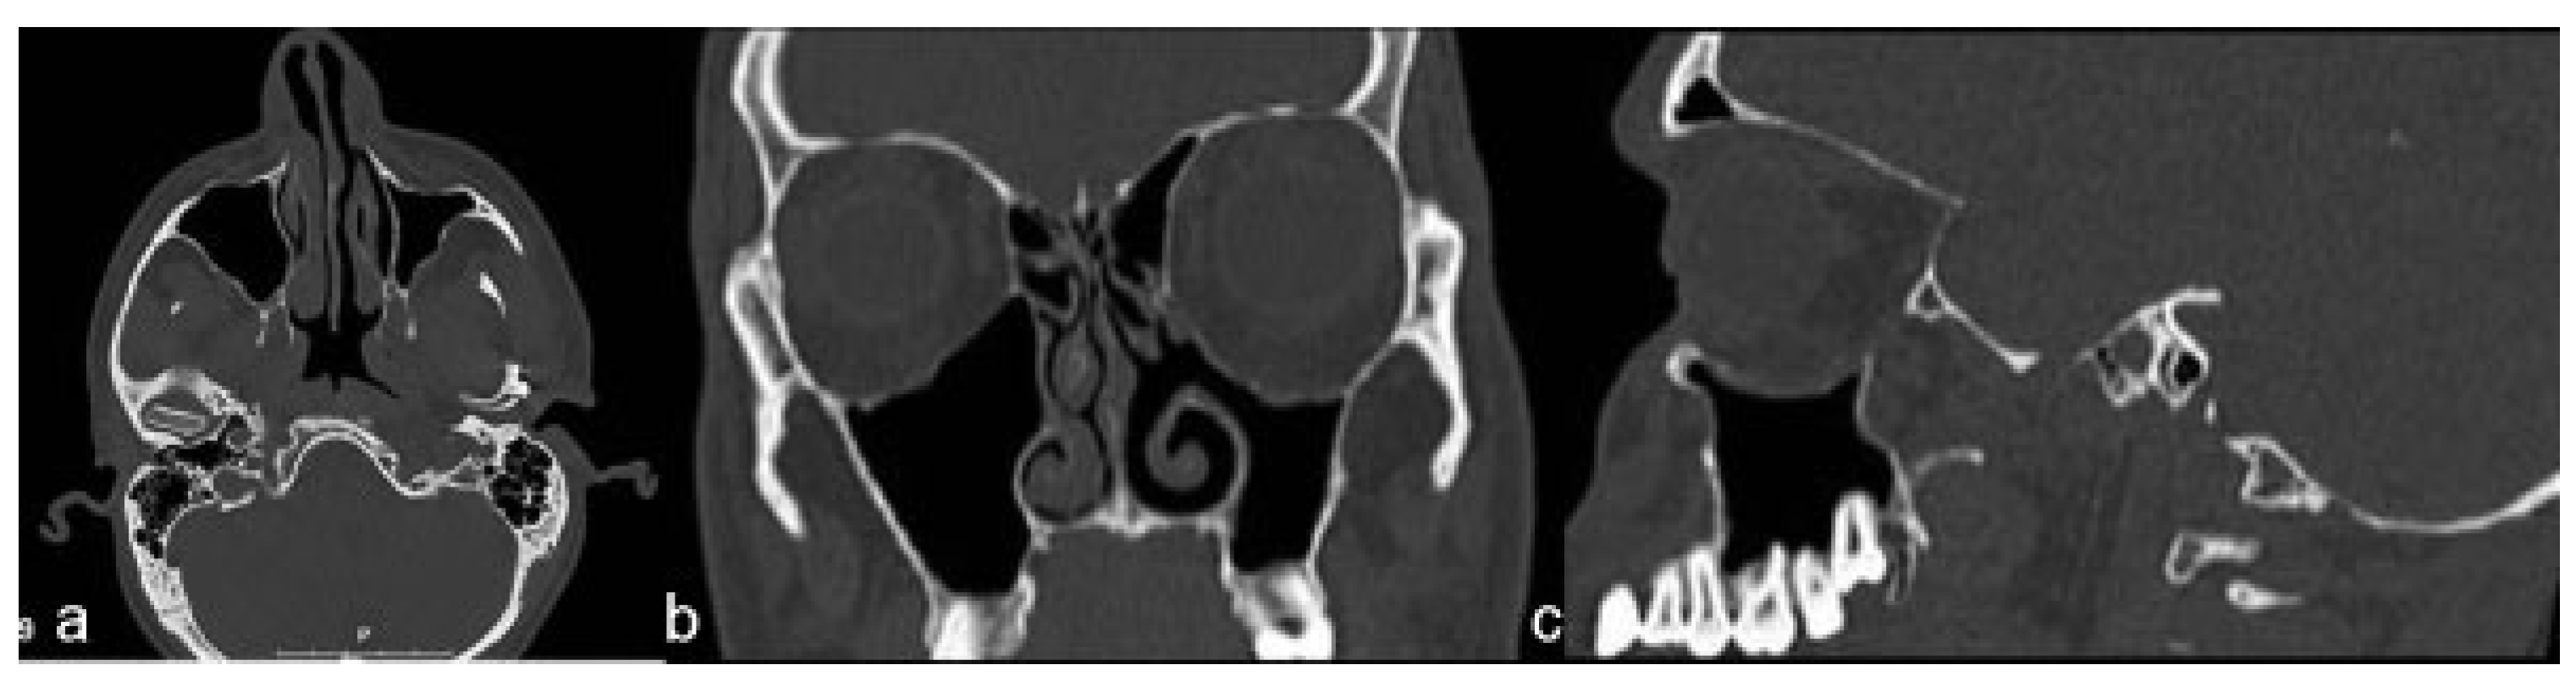

Case Report

- Remodeling and depression of the orbital floor in coronal CT scans.